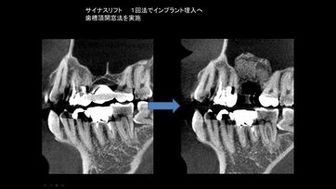

抜歯即時埋入や、サイナスリフト、GBRなど高度な治療も行っています。

インプラント1本埋入のケースでも事前にCTシミュレーションを行い、副鼻空との関係や、下顎臼歯部なら下顎管との距離や補綴する歯との位置関係を把握します。

シビアなケースでは1本でもサージガイドを作製するなど安心安全なインプラント治療を行っています。

ソケットリフトにより骨造成を行った症例

サイナスリフトにより上顎洞の横から

骨に穴を開け骨造成を行った症例